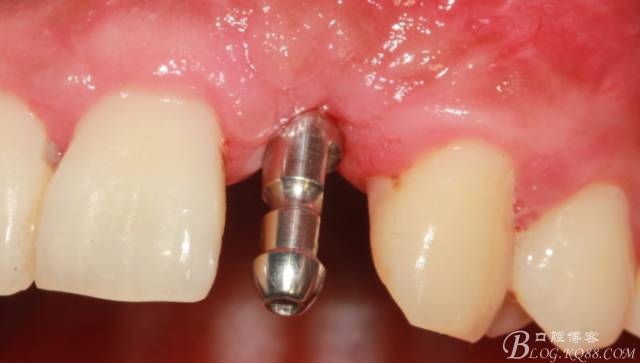

取模。

骨高度穩(wěn)定。

制作臨時(shí)冠。

臨時(shí)冠戴入。